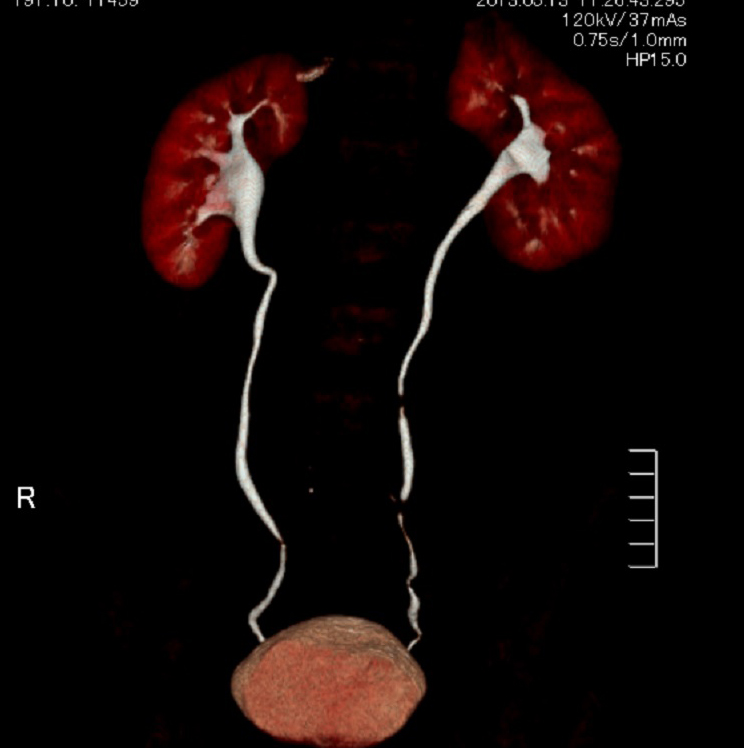

マルチスライスCT

下記など多くの診断ができます。

マルチスライスCT 診断画像

マルチスライスCT 診断画像

- 尿管・腎臓・膀胱